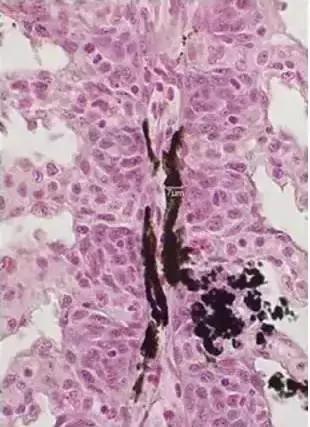

(鳃丝上的黑色素细胞组织切片观察)

黑色素细胞分枝“ 纤细 ”,鳃组织切片观察分枝宽度一般不超过7μm,细胞中的色素颗粒不足1μm,色素颗粒必须在高倍镜下才能见到。